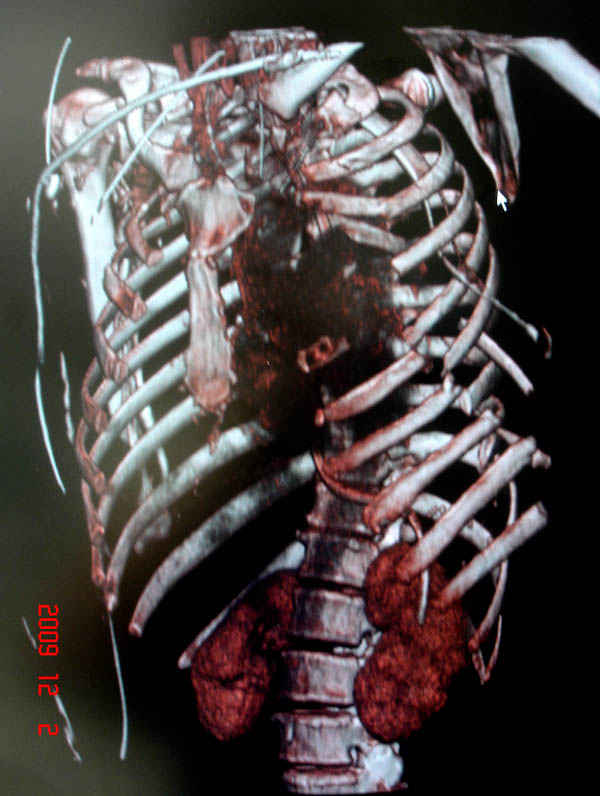

К нам поступила больная 56 лет после автоаварии в бессознательном состоянии, которая срочно заинтубирована в приемном отделении и сделаны необходимые исследования. Данные КТ и рентген показали перелом дистального бедра и Dissociation upper extremity - закрытый отрыв левой верхней конечности на уровне грудинно-ключичного сочленения и множественные переломы ребер.

На поверхности грудной клетки из-за полного разрыва грудной мышцы под кожей заметно биение сердца и след от ремня безопасности. Грудная клетка расширена из-за смещения верхней конечности вверх и латерально. Признаков васкулярного повреждения нет, и из-за отсутствия сознания не смогли определить наличия повреждения нервов.

На седьмые сутки нами совместно с торакальным хирургом сделана операция по фиксации грудинно-ключичного сочленения и переломов ребер.

Не все переломы ребра фиксированы, и поэтому хотели услышать комментарии тех, у кого имеется опыт.

В основном переломы ребер мы тоже не фиксируем, но учитывая, что в данной презентации, кроме разрыва грудинно-ключичного сочленения, дополнительно имелись множественные переломы ребер, некоторые сегментарные. После такой травмы трудно восстановить функцию западающей грудной клетки, и поэтому после дисскуссии с торакальным хирургом мы коллективно приняли решение зафиксировать переломы ребер тоже.